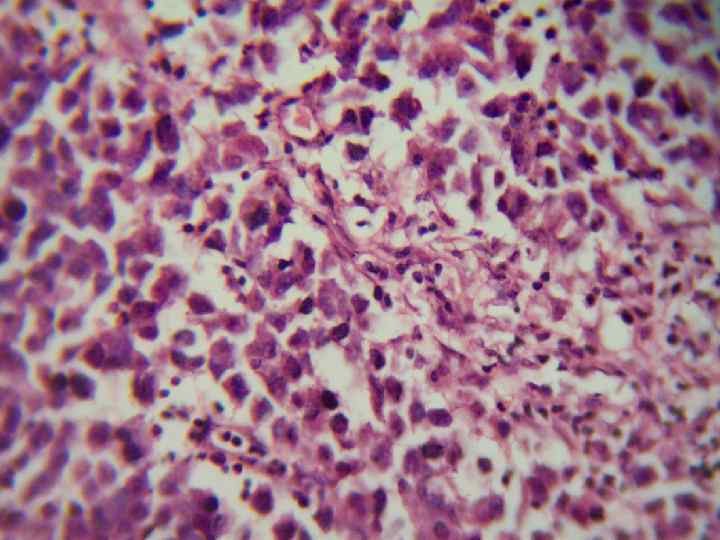

Семинома